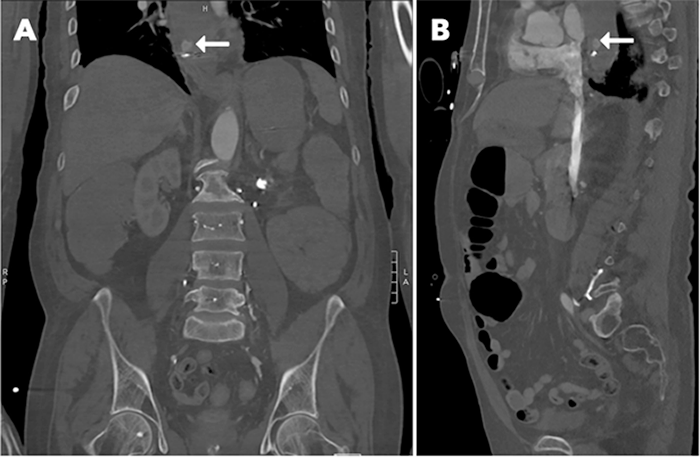

His sequential organ failure assessment (SOFA) score predicted 50 percent mortality at the time of admission. Computed tomography angiography (CTA) of the abdomen and pelvis demonstrated active distal esophageal arterial extravasation adjacent to the previously placed endoclip (Figure 1).

Figure 1. CTA Abdomen and Pelvis with A) Coronal and B) Sagittal Views. Published with Permission

Evidence of active arterial extravasation (denoted by arrows) in distal esophagus adjacent to endoclip and 5 cm proximal to gastroesophageal junction